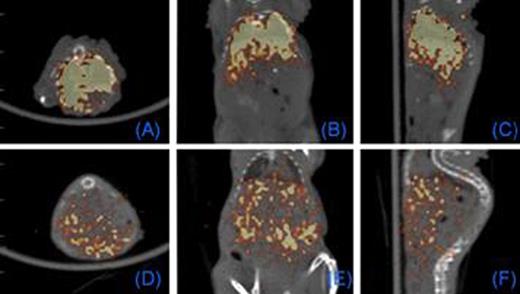

We first tested whether commercially available nanoparticles can be electro-transferred into cultured and primary human T cells. 43 nm diameter latex nanoparticles and 7 nm gold nanoparticles (GNPs) were electro-transferred into T cells and visualized by TEM and confocal imaging (Figure 1). We have modified GNPs on the surface with the chelator, diethylenetriaminepentaacetic acid (DTPA), for stable coordination with 111In followed by GNP PEGylation. We have shown that these radiolabeled GNPs can be readily electro-transferred into T cells suitable for combined single-photon emission computed tomography (SPECT) and computed tomography (CT) (Figure 2). We used a clinical SPECT/CT scanner to detect 111In-GNP in T cells (∼2.1 × 104 nanoparticles/cell) at a sensitivity of ∼760 cells/mL. After developing electroporation protocols of nanoparticles and in vivo imaging of 111In-GNPs, additional sensitivity was achieved by modifying the chelating chemistry using the macrocyclic chelator, 1,4,7,10-tetraazacyclododecane-1,4,7,10-tetraacetic acid (DOTA), to bind 64Cu to GNPs, increasing the number of gold particles/cell, and using 64Cu-labeled GNPs for imaging by positron emission tomography (PET). Before tail vein injection to a mouse, 11.4 mCi was detected from 10 million T cells (suspended in 300 μL PBS) electroporated using a BTX ECM830 device with the following settings: 1 kV/cm, 4 ms duration, single square pulse (Figure 3). The estimated concentration of nanoparticles transferred into T cells was ∼2.3 × 105 nanoparticles/cell as determined by a gamma counter (2470 Wizard, PerkinElmer) and nanoparticle titration. While 20 nm GNPs were used for 111In labeling, 7 nm GNPs were chosen for 64Cu labeling because of the improved (10-fold) electroporation efficiency.

PET Imaging of T cells loaded with intracellular 64Cu-GNPs. 0.5 (A-C) and 18 (D-F) hours after tail vein injection of T cells. Each panel: axial, coronal, sagittal views, respectively.